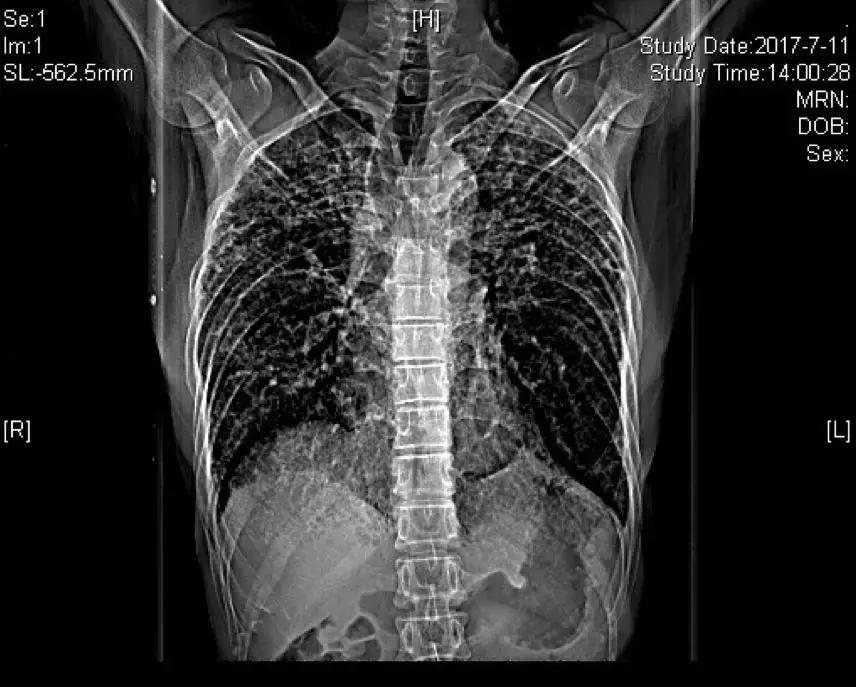

胸部正位片(2018-03-01):

胸部正位片(2018-06-01):最后一次